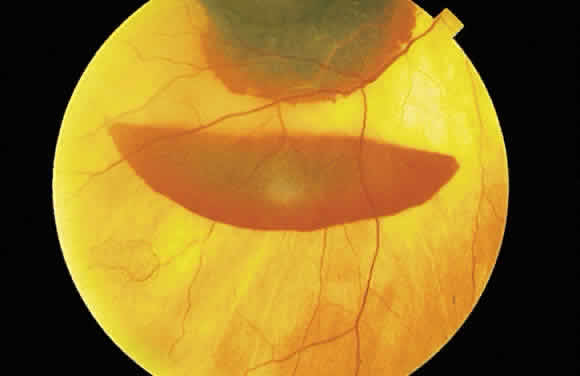

The location of the hemorrhage also may affect is ophthalmoscopic appearance. Fresh hemorrhage between the retinal pigment epithelium and Bruch's membrane may appear brown or red-black, in contrast with the bright red color seen in fresh hemorrhages anterior to the pigment epithelium (see Fig. 13A). The location of hemorrhages within the retina also accounts for the shape of the lesion. Blood that accumulates between the nerve fiber layer and the internal limiting membrane (subinternal limiting membrane hemorrhage) (Fig. 57) assumes a shape defined by gravity, meniscus or boat-shaped, when the patient is upright (Fig. 58). The name subinternal limiting membrane hemorrhage is technically ambiguous, since a hemorrhage in the outer plexiform layer also is below (sub) the internal limiting membrane.

Fig. 58. Hemorrhage located just beneath the internal limiting membrane with the patient in the upright position. The retinal vessels are visible on the surface of the layered hemorrhage.